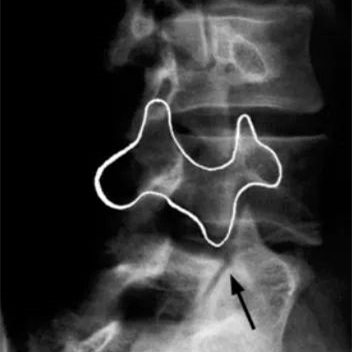

腰椎斜位X片上的“狗”症

①狗嘴巴為近膠片側橫突

②狗眼睛為近膠片側椎弓根

③狗耳朵為近膠片側上關節突

④狗脖子為近膠片側椎弓峽部

⑤狗身體椎弓板

⑥狗下關節突

⑦狗尾巴為遠膠片側的橫突